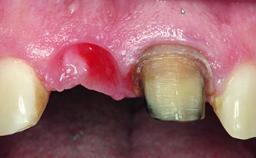

A 32-year-old female Caucasian patient with a compromised maxillary right central incisor was referred to us by a general dentist. Her chief complaints were discomfort and mobility of tooth 11 with unsatisfactory esthetics due to discoloration. The patient reported a previous trauma, some years earlier, as the origin of pathology on the afflicted tooth. Anamnesis was negative for any other dental or periodontal pathology in the remaining dentition. The patient did not take any medication and reported to be a light smoker (5–10 cigs/day). She had high esthetic expectations of her treatment. The extraoral examination revealed a high smile line with full exposure of her maxillary teeth and surrounding soft tissue in the area between the second premolars.

Soft Tissue Anatomy Intact Defective

Bone Volume Horizontally and vertically sufficient Horizontally deficient Deficient vertically or deficient vertically AND horizontally

Soft Tissue Contour and Volume Slightly compromised